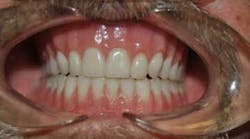

Kevin recently received his brand new set of teeth, and he can't stop smiling.

"I feel wonderful!" says Kevin, laughing. "I look in the mirror and I smile at myself. I can't believe that's me! And being able to smile at people, and they smile back. I don't scare them anymore."

His wife has also observed the changes that have occurred for her "miracle man," as she likes to call him.

"Oh, he's so proud of his teeth! He's so proud of them," says Cindy. "He looks in the mirror and he went for so long with bad teeth, then no teeth, and he got in the habit of covering his mouth with his hands when he would laugh. He loves his teeth! The people at Rodeo Dental are just amazing, amazing people."